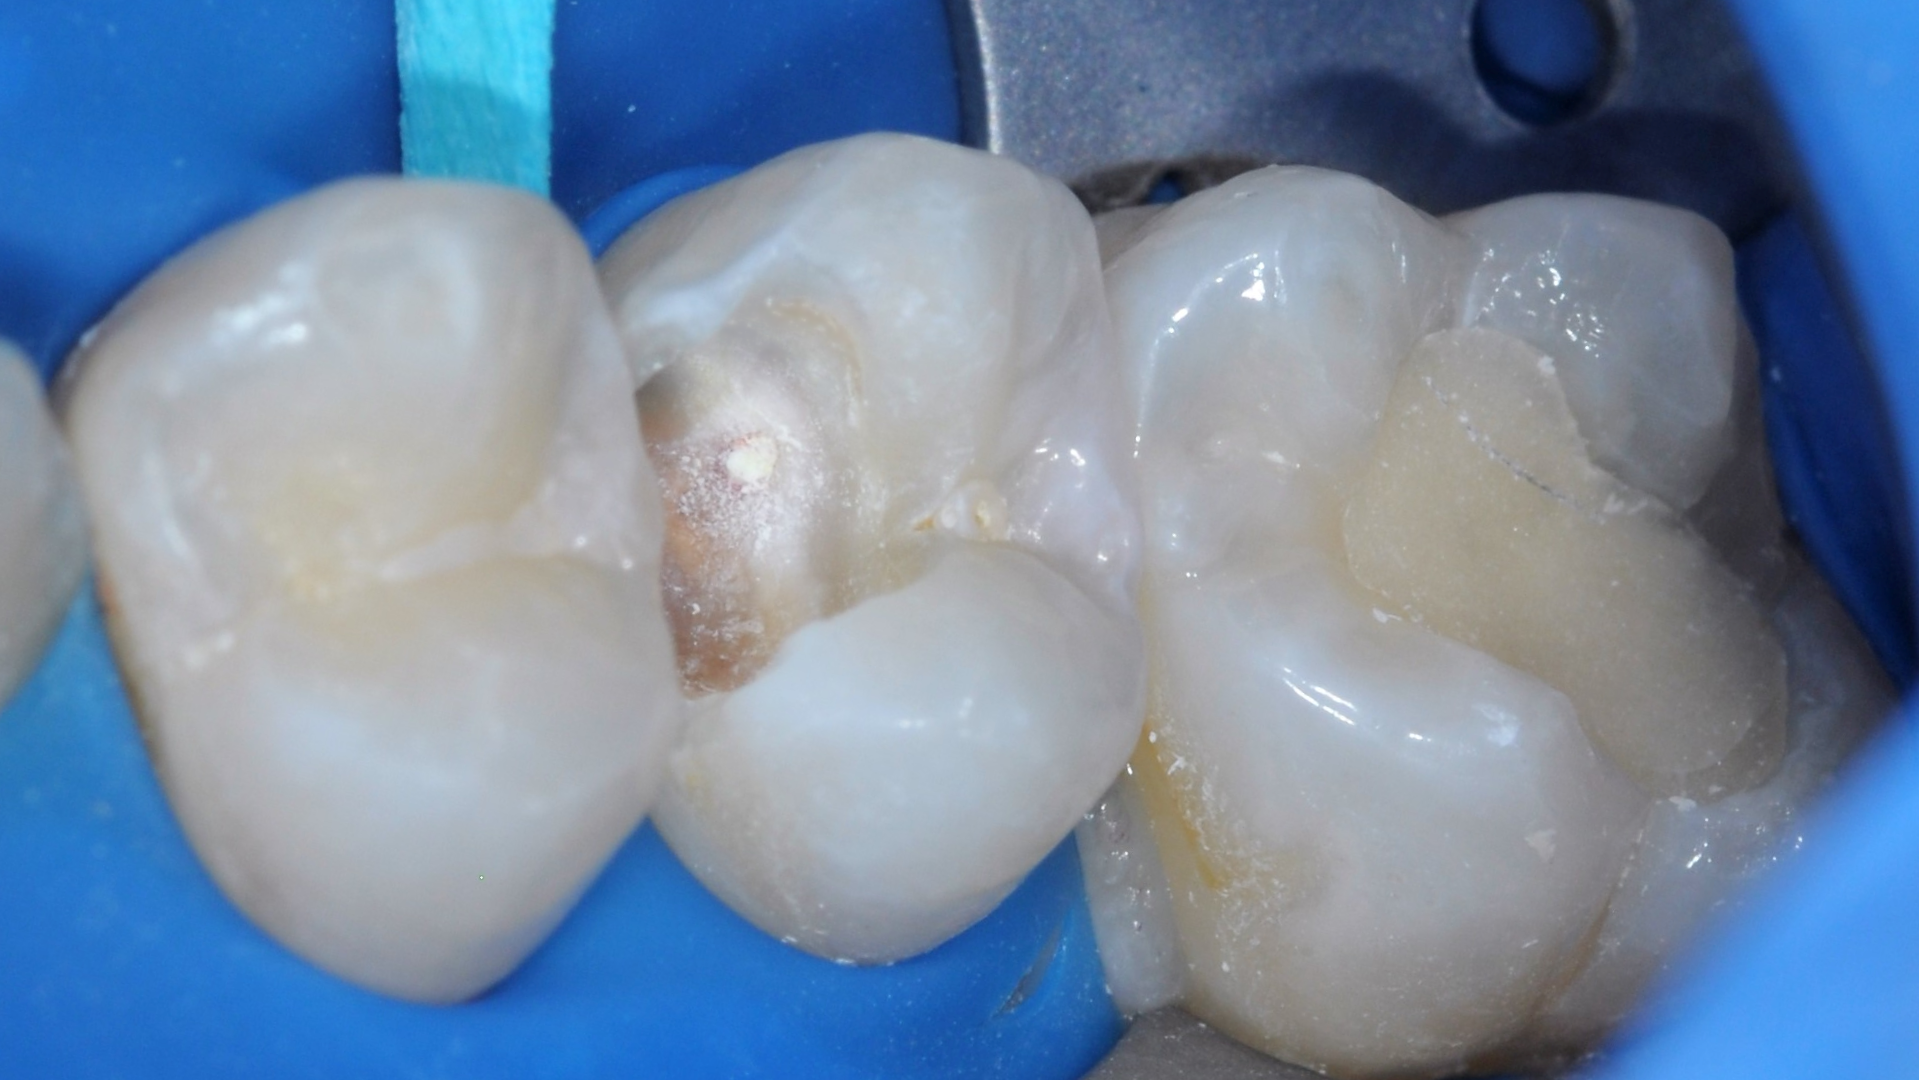

Leczenie zachowawcze zęba 15 rozpoczęto od testu żywotności (reakcja na bodziec zimny prawidłowa). Wykonano znieczulenie nasiękowe oraz izolację pola zabiegowego koferdamem (Rubber-Dam, Cerkamed) (ryc. 1). Ubytek opracowywano zgodnie z wytycznymi Europejskiego Towarzystwa Endodontycznego (European Society of Endodontology – ESE) w sprawie leczenia próchnicy głębokiej i obnażeń miazgi (1). W pierwszej kolejności, w powiększeniu, przy użyciu mikroskopu, wiertłem diamentowym na końcówce przyspieszającej usunięto próchnicowo zmienione szkliwo. Następnie wiertłem różyczkowym na mikrosilnik usunięto zainfekowaną bakteryjnie zębinę na peryferiach ubytku (infected dentine, soft dentine). Zbliżając się do komory zęba, zmieniono wiertło na sterylne i na niskich obrotach usuwano kolejne partie zębiny zainfekowanej. Podczas końcowej fazy opracowania ubytku doszło do próchnicowego obnażenia miazgi (obnażenie miazgi klasy II według ESE) (1) (ryc. 2). Zębinę zdemineralizowaną (affected dentine, firm dentine) pozostawiono w dnie ubytku. Krwawienie z miejsca obnażenia zahamowano sterylną gąbką, nasączoną roztworem 0,9-procentowym NaCl, uciskając przez 5 minut. Obnażenie zaopatrzono materiałem na bazie MTA (BIO MTA +, Cerkamed) i pozostawiono do wstępnego związania przez 12 minut (ryc. 3).

Ryc. 2. Próchnicowe obnażenie miazgi.

Ryc. 3. Przykrycie bezpośrednie (BIO MTA +, Cerkamed). Na ścianie dokomorowej widać firm dentine.